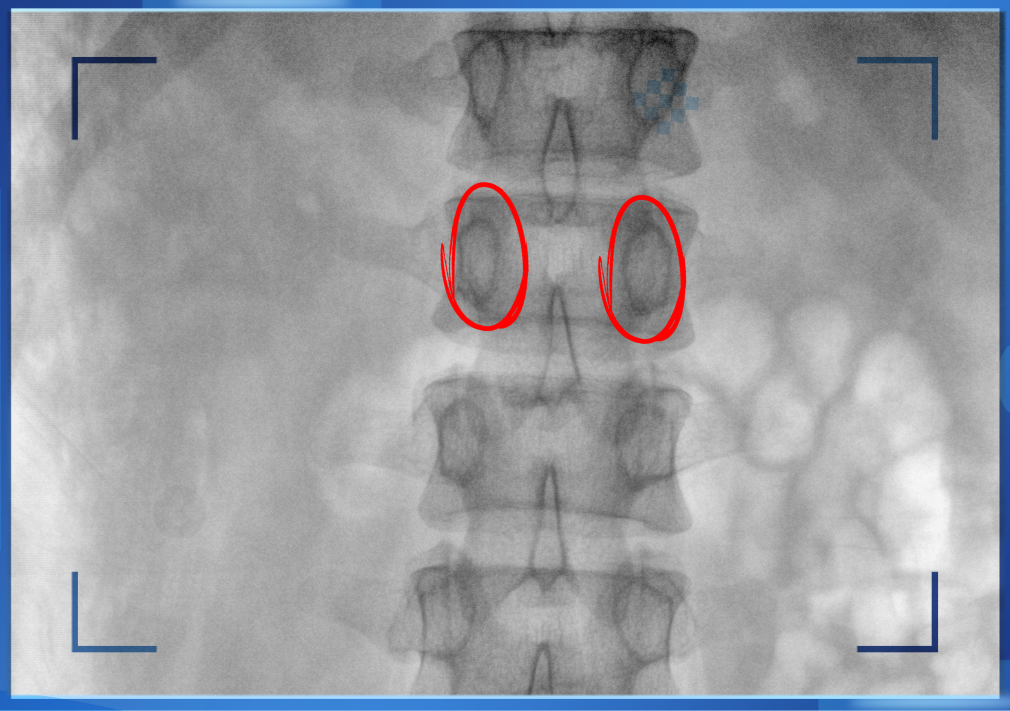

医生通?;嵩凇懊ㄑ邸崩镅罢医氲愫统稣氲?,凭医生的经验把钉子打在椎弓根里。手术比较依赖医生的经验,万一出现偏差对病人来讲就是毁灭性的打击。如果在复杂的手术中有三维影像的支持,确保钉子精准的打在椎弓根里,可大大的提高手术操作的精度。

“猫眼”指的是椎弓根在正位的投影。